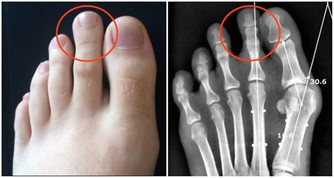

哪些腎病患者需要控制飲水呢?是那些腎臟排水功能受損的患者。

臨床上認為,“少尿”的標準是每天少於400ml,

“無尿”的標準是每天少於100ml,這些腎病患者是需要控制飲水的。